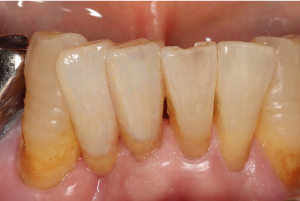

症例

メリーランドブリッジ

治療前

治療後

下の前歯が1本欠損している状態です。通常のブリッジでは欠損している両横の歯を削ります。このケースでは犬歯が傾いていますので歯を削る量が通常より多くなってしまいます。今回は欠損している右隣の裏側を薄く削ってセラミックブリッジ接着しました。